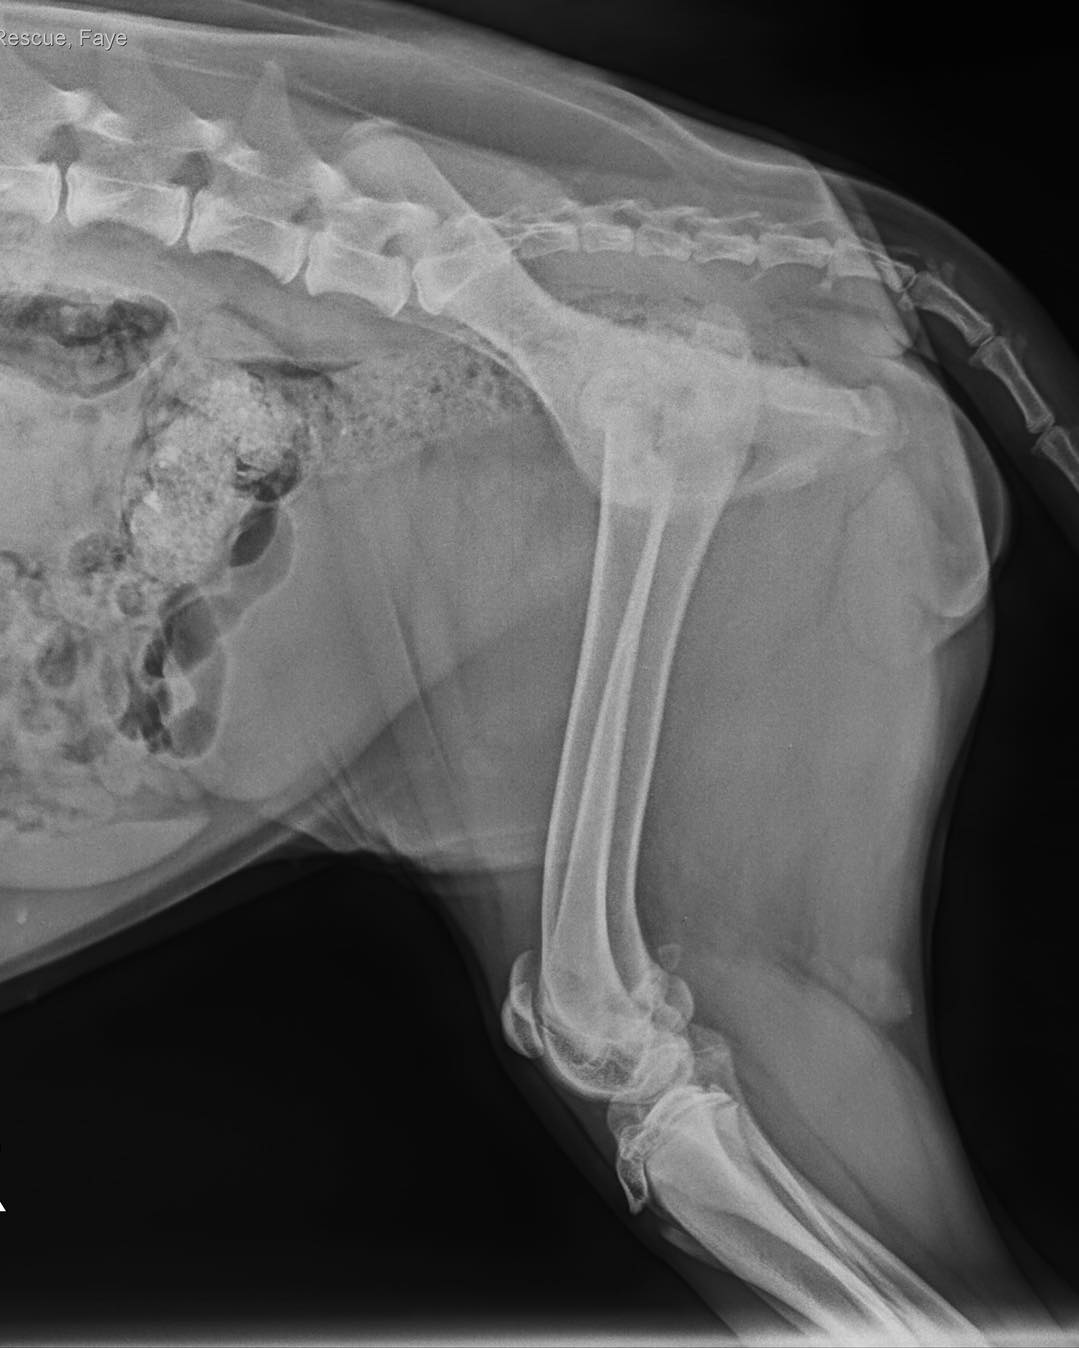

21Aug17 Surgeries (6)